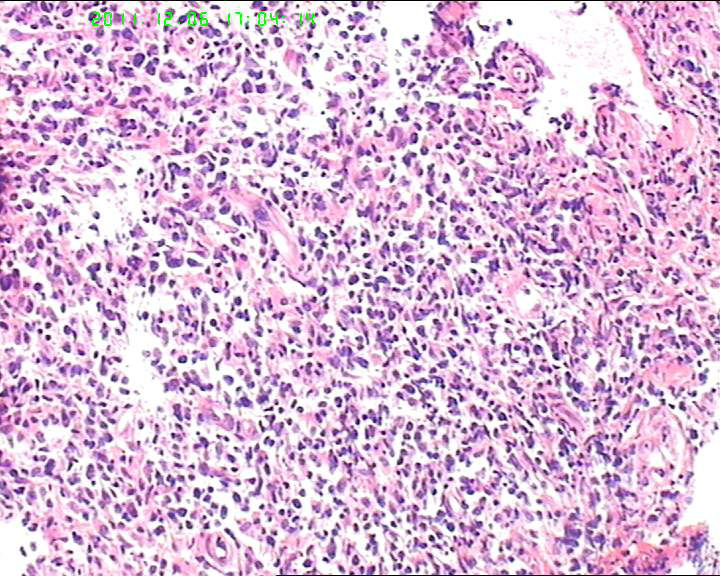

横纹肌肉瘤,恶黑,NK/T

细胞异性明显,弥散分布,可见血管内皮异性明显,首先考虑血管肉瘤,恶黑,淋巴瘤?

组织内见大量形态各异的异型明显的细胞,弥漫分布,背景见肿瘤素质,首先考虑结外NK/T细胞淋巴瘤,鼻型;恶黑待排。

恶性淋巴瘤(NK/T)

横纹肌肉瘤,恶黑,血管肉瘤,NK/T等